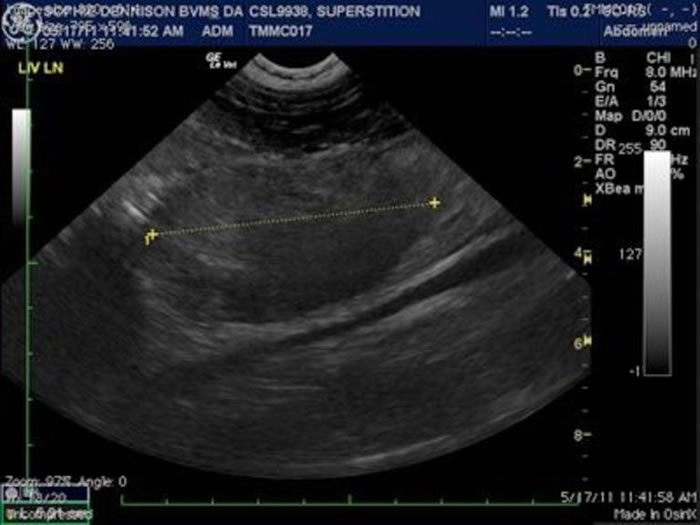

海洋哺乳动物中心为一只加州海狮照超音波,测量腹部肿瘤。这只昵称为「迷信」的海狮死于癌症。 PHOTOGRAPH BY THE MARINE MAMMAL CENTER

某个位在加州索萨利托(Sausalito)办公室的门骤然打开,原来是艾莉莎·戴明(Alissa Deming)忙着为一只搁浅的加州海狮做超音波检查,但她还需要上司─ ─钻研海洋哺乳类癌症廿年的兽医主任弗兰西斯·格兰德( Frances Gulland )的意见。

戴明说:「症状包括子宫扩张与内膜增厚,我想这属于子宫内膜异位(endometriosis)的病例。」她是非营利海洋哺乳动物救伤与研究中心的动物病毒学家,该中心位于马林岬,与旧金山相望。

戴明认为加州海狮是生殖相关癌症最新一波的受害者。